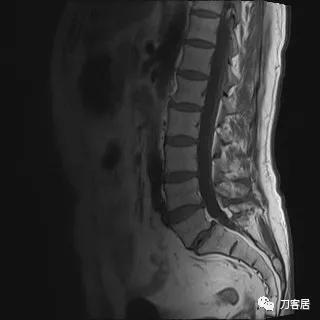

入院后予以腰椎CT及MRI检查,未见明显之椎间盘突出及椎管狭窄。

图13. 20210626术前腰椎MRIT1相1

图14. 20210626术前腰椎MRIT1相2